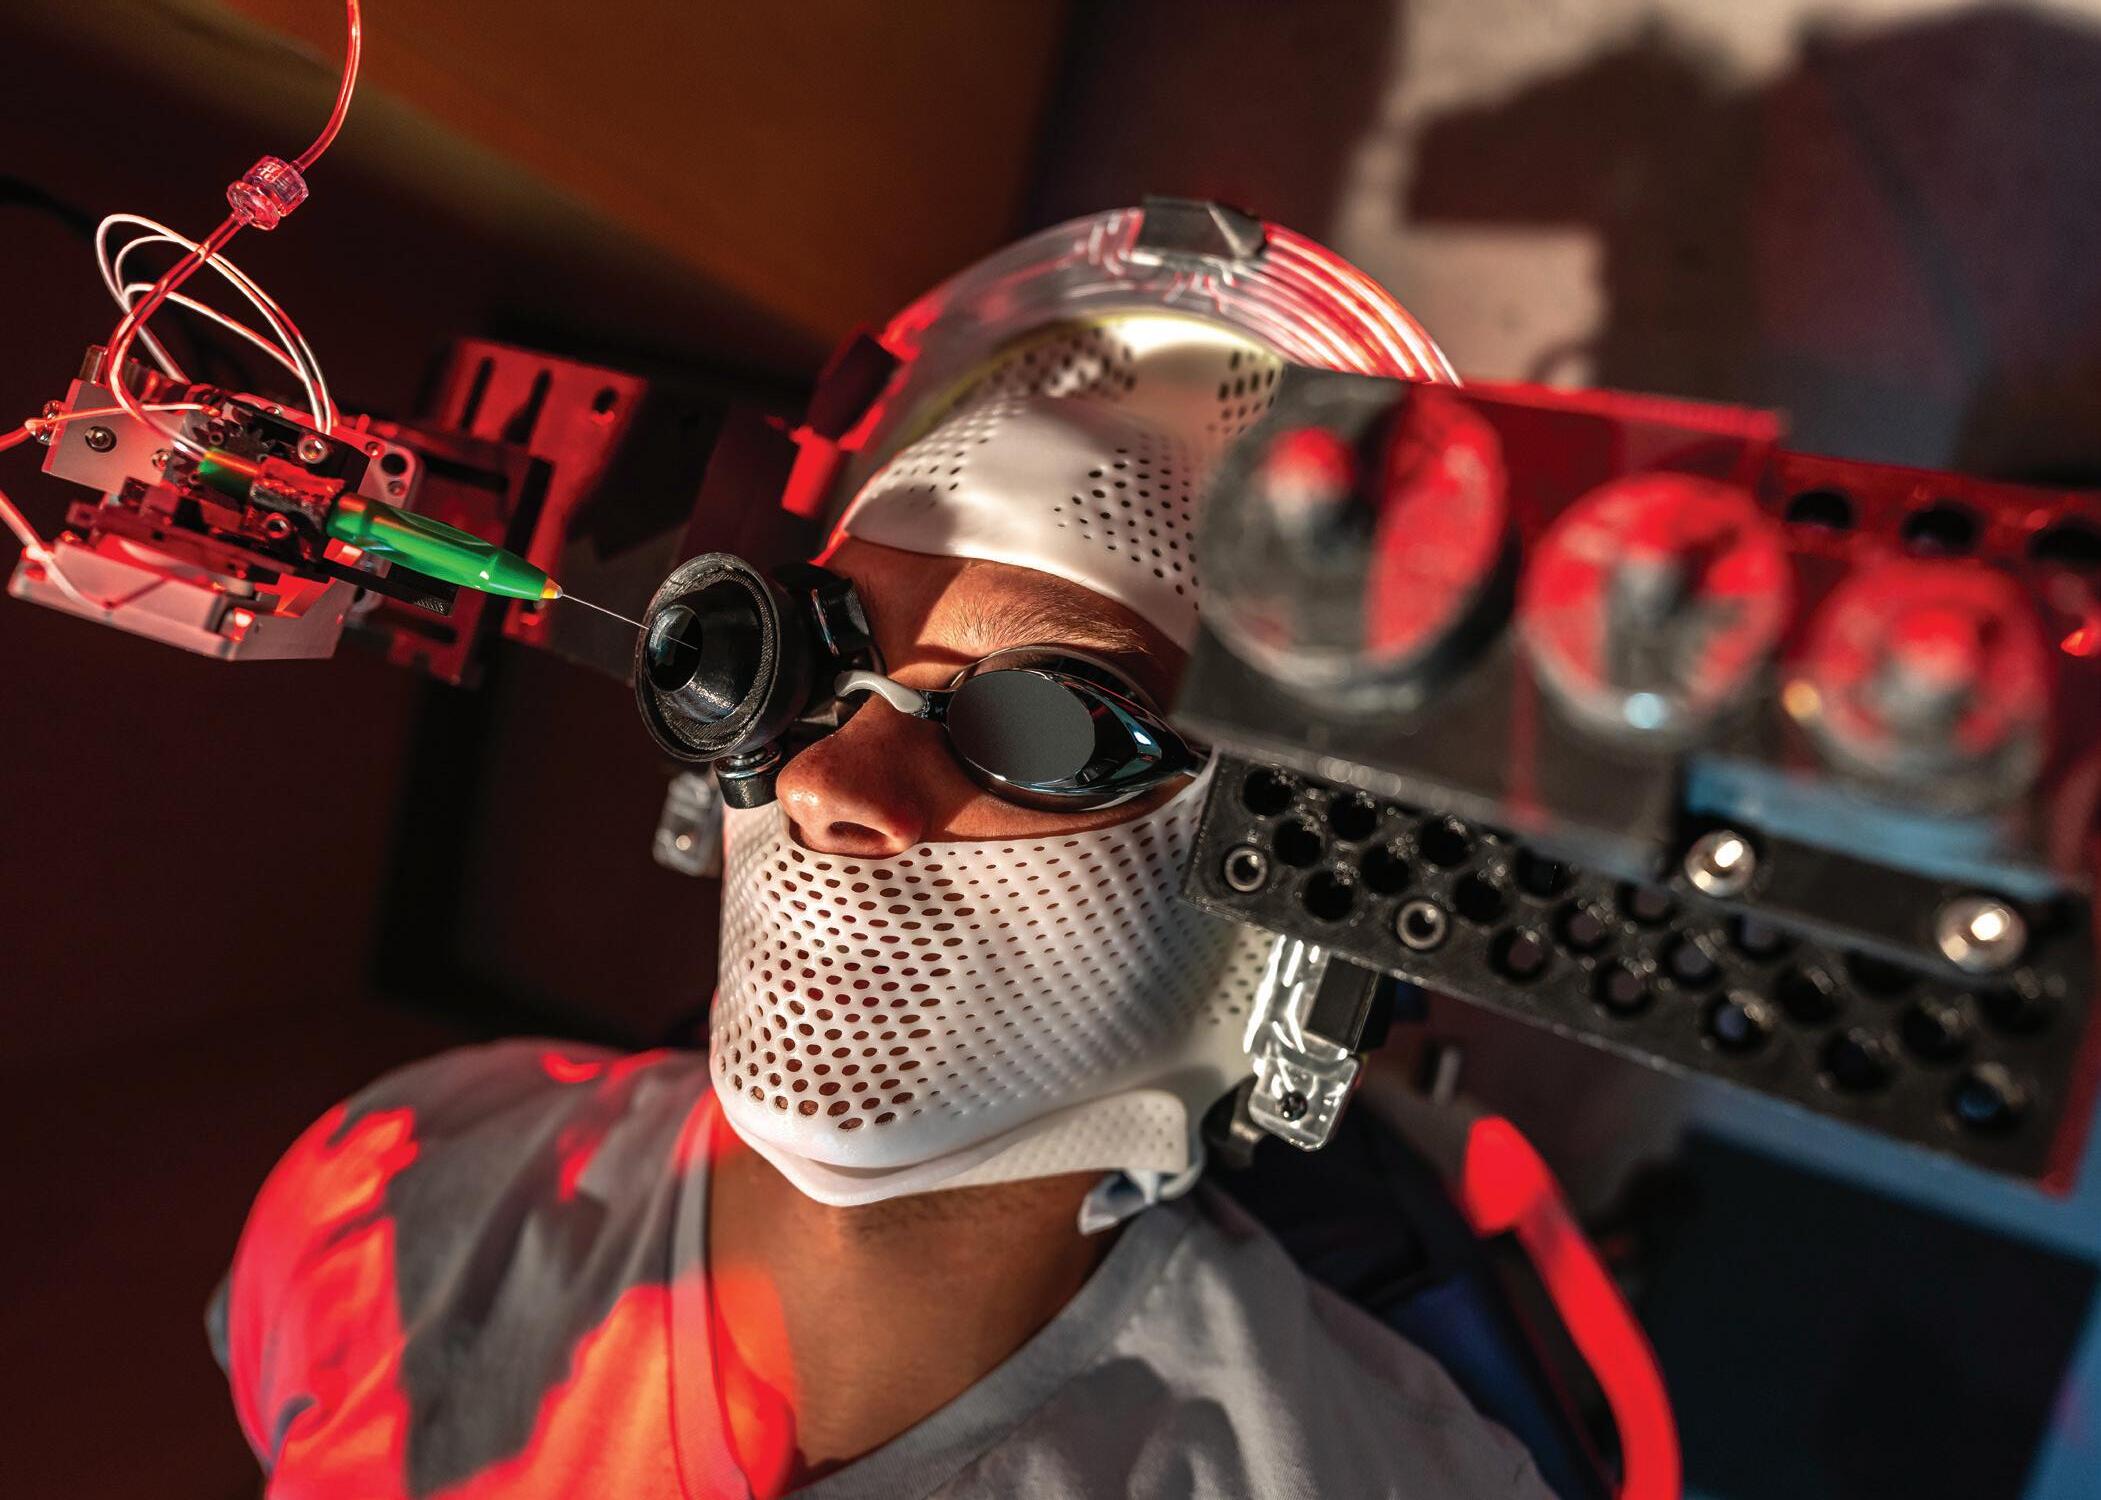

The Future of Eye Surgery

A Moran lab and campus robotics colleagues are developing a new device with the potential to transform eye surgery.

Spaces in the back of the eye below the retina measure just fractions of a millimeter—a tight spot for talented surgeons with steady hands to access even under the best of circumstances.

If a sedated patient snores or moves slightly, surgery can become even more challenging.

A new robotic eye surgery device developed by Moran’s Paul S. Bernstein, MD, PhD, and the University of Utah Magnetic & Medical Robotics Laboratory aims to transform retinal surgery by increasing precision and safety.

“Robotic surgery is the future, allowing us to go past the limits of what humans can do,” says Bernstein, a retinal specialist and scientist. “This device, in particular, is important as many new therapies, including gene therapies for retinal diseases like age-related macular degeneration, must be delivered by subretinal injections into this minute space in the eye.”

During eye surgery, patients are typically under some level of sedation but not general anesthesia. They may snore or make sudden movements, which can increase the risk of injury to the patient’s retina, a delicate layer of light-sensing tissue essential for vision.

The noninvasive device consists of a helmet-like structure worn by the patient. A small robot is attached to the structure, which moves with the patient. A surgeon controls the robot by using a joystick device that filters out any hand tremors.

Experiments have shown the device to be highly successful at preventing complications due to patient movement, says Ja ke Abbott, PhD, director of the robotics lab.

“We think of our robots as tools for surgeons,” he says.

Researchers have been testing the device on animal eyeballs resting on swim goggles worn by human volunteers. This allows them to evaluate the precision of the device under realistic conditions.

“This patient-motion aspect has been neglected in a lot of other research,” says Nick Posselli, a graduate student in mechanical engineering who has worked with Abbott to develop the device over the past seven years.

Since only a small number of surgeons are qualified to perform subretinal injections, the device could increase the number of surgeons who can perform them.

“Retinal surgery is a technically difficult surgery and takes a while to master, so for people in the earlier stages of their career, having robotic assistance can ma ke it safer and more effective,” Bernstein says.

Bernstein praised the cross-disciplinary collaboration with University of Utah engineers. The group anticipates publishing new results in the near future.

“The next step,” he says, “is to refine the system that’s working well on these models so we can take it to the next stage, which is human use.”